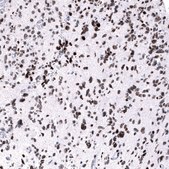

immunofluorescence: 2-10 μg/mL (ICC-IF), immunohistochemistry: 1:500 - 1:1000

All Prestige Antibodies Powered by Atlas Antibodies are developed and validated by the Human Protein Atlas (HPA) project and as a result, are supported by the most extensive characterization in the industry.

The Human Protein Atlas project can be subdivided into three efforts: Human Tissue Atlas, Cancer Atlas, and Human Cell Atlas. The antibodies that have been generated in support of the Tissue and Cancer Atlas projects have been tested by immunohistochemistry against hundreds of normal and disease tissues and through the recent efforts of the Human Cell Atlas project, many have been characterized by immunofluorescence to map the human proteome not only at the tissue level but now at the subcellular level. These images and the collection of this vast data set can be viewed on the Human Protein Atlas (HPA) site by clicking on the Image Gallery link. We also provide Prestige Antibodies® protocols and other useful information.

• IHC tissue array of 44 normal human tissues and 20 of the most common cancer type tissues.